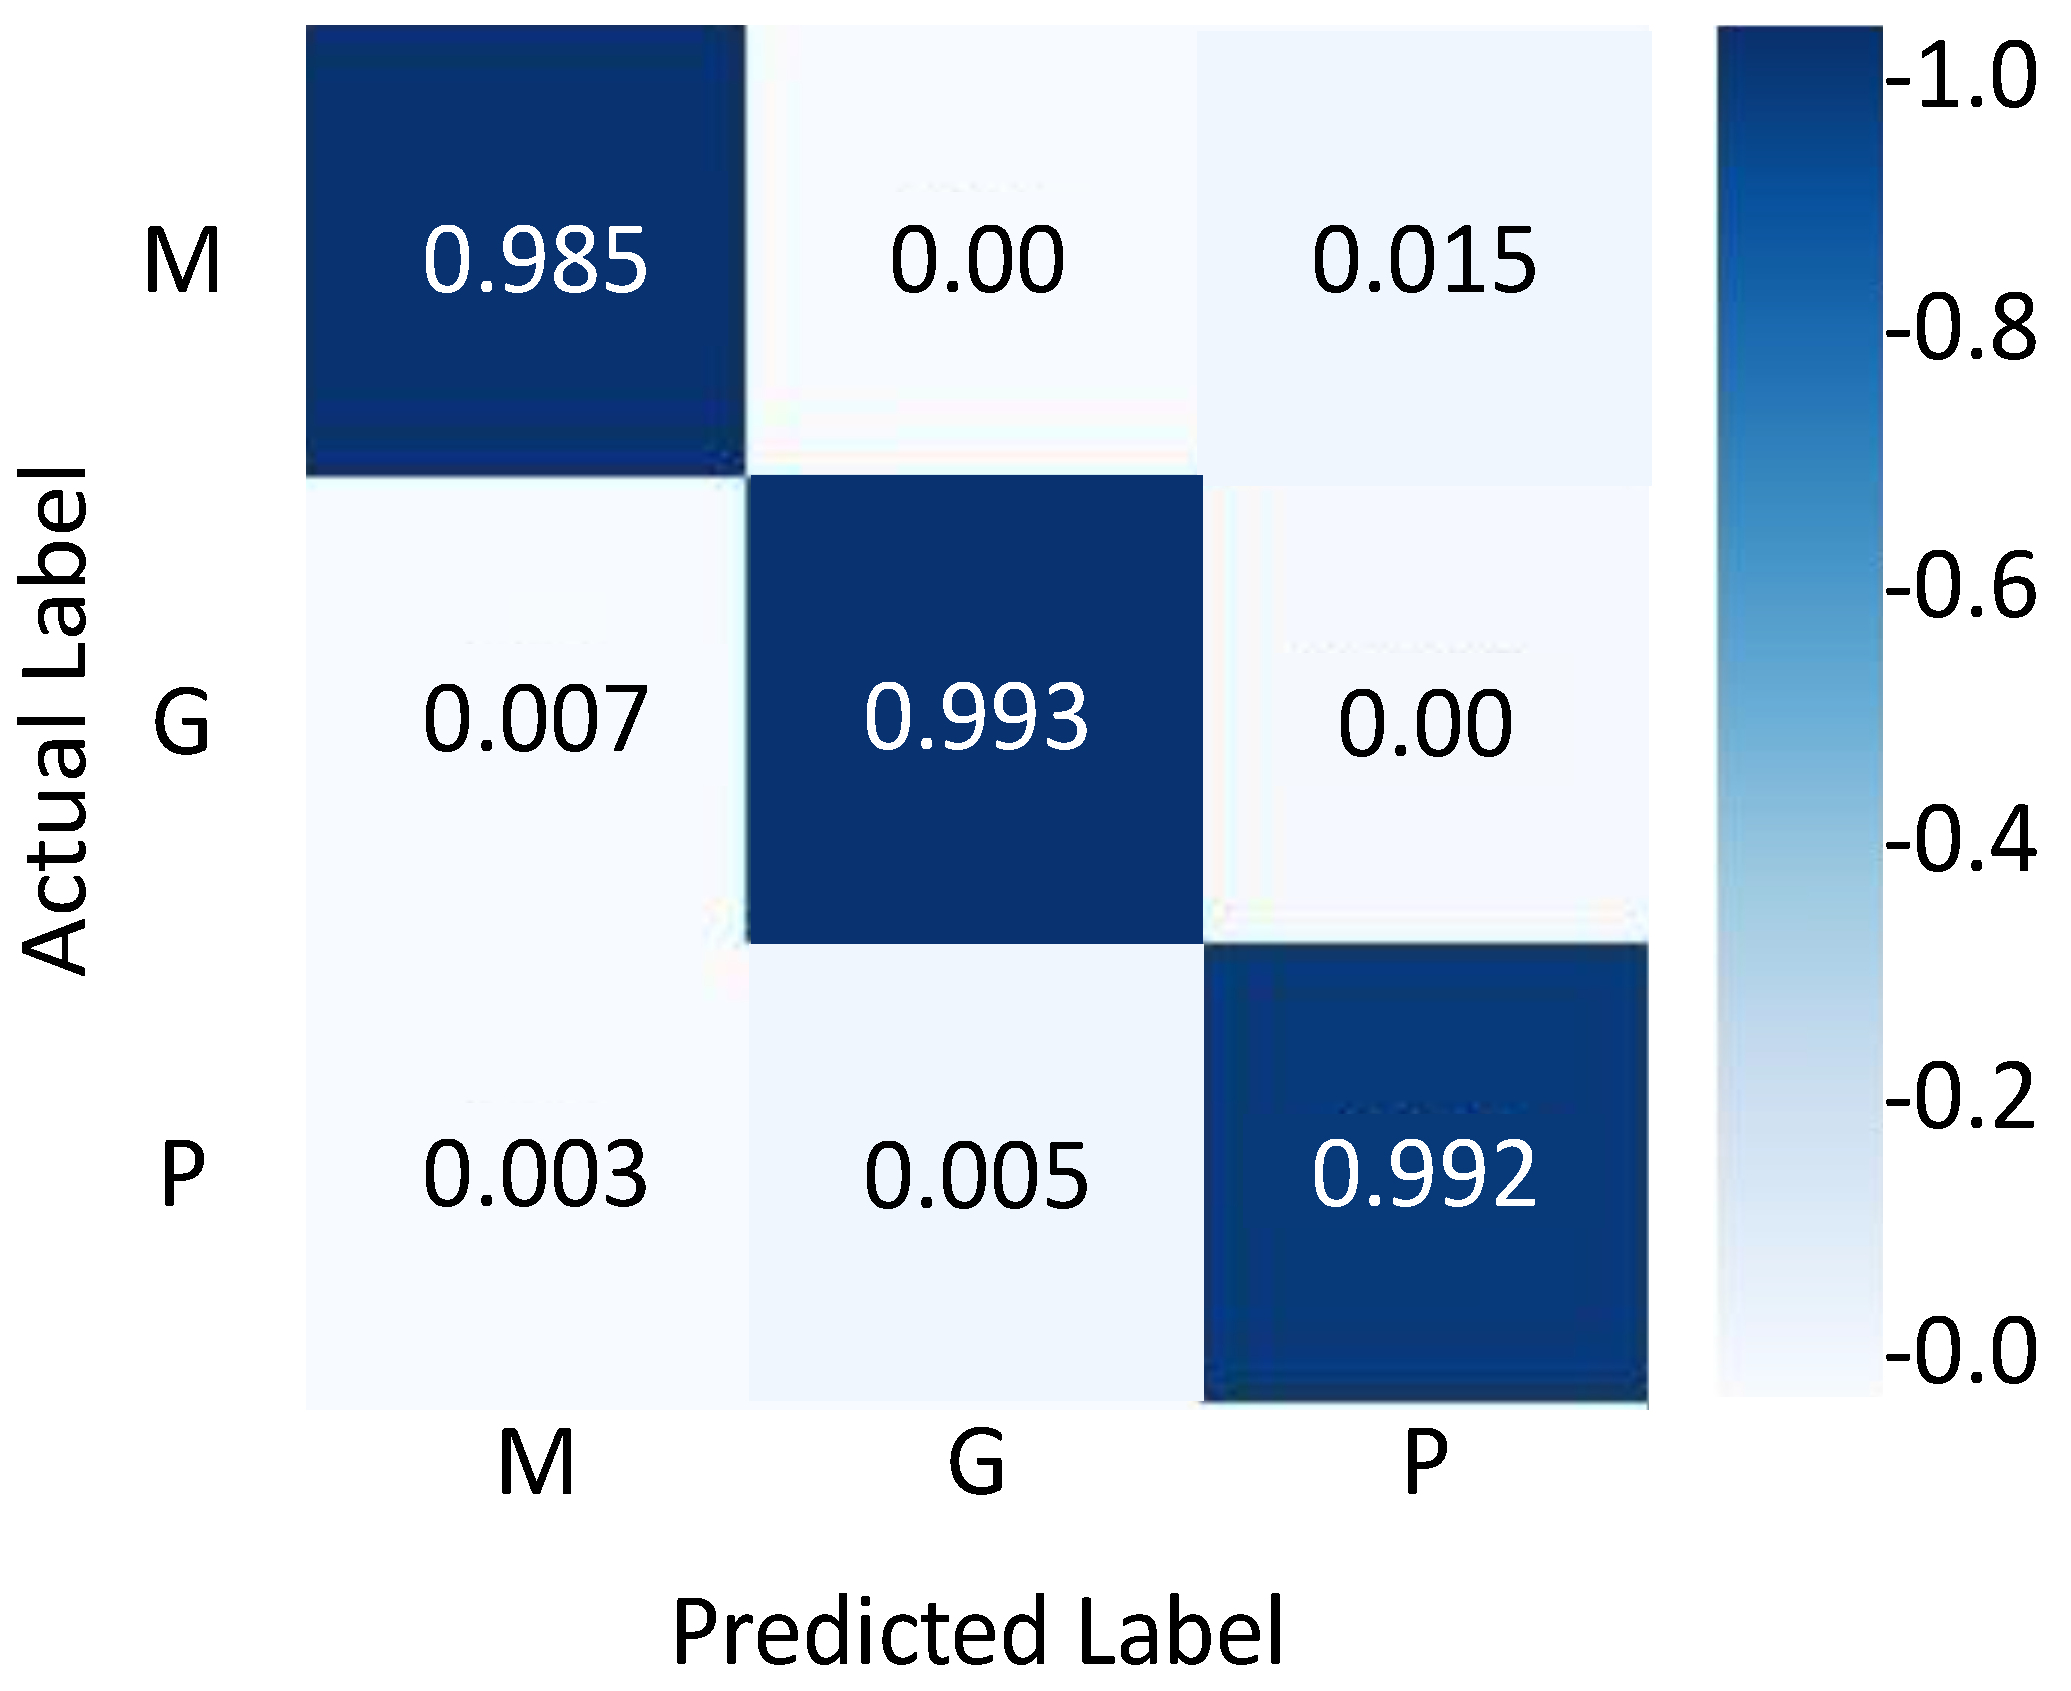

4.4. Results Evaluation Using Figshare Dataset

| Classes | Precision | Recall | F1-Score | Accuracy |

|---|---|---|---|---|

| Meningiomas | 0.99 | 0.99 | 0.99 | 99.35 |

| Gliomas | 0.99 | 0.99 | 0.99 | 99.02 |

| Pituitary tumors | 0.98 | 0.99 | 0.98 | 98.95 |

| Average | 0.987 | 0.99 | 0.987 | 99.10 |

| References | Accuracy |

|---|---|

| Ari et al. [72] | 97.64% |

| Cheng et al. [28] | 94.68% |

| Abir et al. [69] | 83.33% |

| Afshar et al. [76] | 86.56% |

| Cheng et al. [67] | 91.28% |

| Deepak and Ameer [71] | 97.10% |

| Kaur and Gandhi [75] | 96.95% |

| Ayadi et al. [77] | 90.27% |

| Pashaei et al. [78] | 93.68% |

| Swati et al. [74] | 94.80% |

| Deepak and Ameer [79] | 95.82% |

| Bodapati et al. [66] | 95.23% |

| Türkoğlu M et al. [73]. | 98.04% |

| Proposed Model | 99.10% |